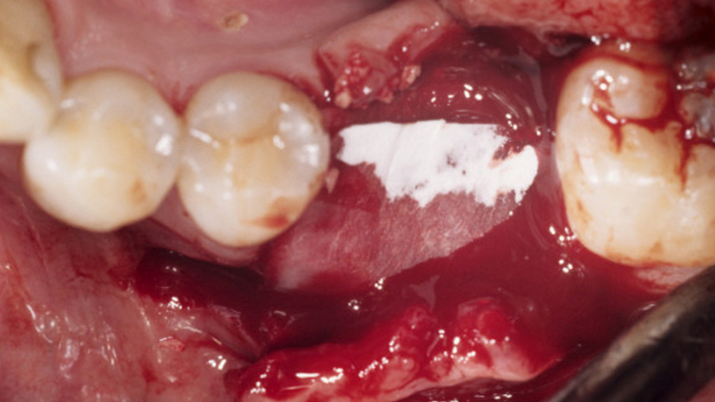

Clinical case: Bone filling into the bottom of deepest thread at 8.0mm AnyRidge fixture

- Courtesy of Dr. Kwang Bum Park -

Keywords

AnyRidge, Knifethread ,extraction socket, ,initial stability ,Allograft, ,osseointegratio ,Dr. Kwang Bum Park, , Mandibular, Single replacement, AnyRidge, Mega-oss,

Products used

Implant system-AnyRidge, Regeneration-Mega-Oss